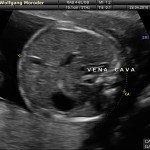

L’ecografia è una tecnica che consente di vedere gli organi del nostro corpo con l’utilizzo di onde sonore ad alta frequenza (ultrasuoni, non udibili dall’orecchio umano) che attraversano i tessuti. La sonda ecografica invia impulsi di onde sonore nel corpo. Quando le onde sonore arrivano al feto mandano degli echi: tali echi (o onde di ritorno) sono trasformati in immagini sul monitor dell’ecografo. Con l’ecografia è quindi possibile osservare in modo dettagliato il feto.

Le ragioni più comuni per cui si esegue una ecografia in gravidanza sono: determinare il numero degli embrioni o dei feti, visualizzare l’attività cardiaca fetale, determinare l’epoca di gravidanza, valutare l’anatomia e la crescita fetale, determinare la posizione del feto e della placenta

Nei primi mesi di gravidanza, con la misura della lunghezza del feto, è possibile valutare se lo sviluppo corrisponde all’epoca di gravidanza valutata in base alla data dell’ultima mestruazione, il numero dei feti e la presenza dell’attività cardiaca.

Dal secondo trimestre si misurano altre parti fetali, ed i valori di tali misure vengono confrontati con quelli delle curve di riferimento. Si può così valutare la normalità o meno della crescita fetale. Inoltre periodo si visualizzano la sede di inserzione placentare e la quantità di liquido amniotico.

A fianco alla più tradizionale ecografia eseguita per via transaddominale, risulta particolarmente utile nell’esame ecografico ostetrico e ginecologico la via di accesso transvaginale.

Con questa metodica, utilizzando delle sonde ecografiche appositamente predisposte (per forma e dimensione, e per frequenza di emissione degli ultrasuoni) è possibile controllare la gravidanza nel primo trimestre con una qualità e definizione d’ immagine nettamente superiori a quanto possibile per via transaddominale.

Con l’ecografia transvaginale è possibile vedere dopo circa 3 settimane dal concepimento la camera gestazionale nella cavità uterina. Successivamente è possibile visualizzare l’embrione (3-5 mm.) a circa 6 settimane dall’ultima mestruazione (4 settimane dal concepimento) ed a questo periodo è già visibile l’attività cardiaca fetale Anche i primi dettagli sulla morfologia fetale (polo cefalico, abbozzi degli arti) sono visualizzabili più precocemente con l’ecografia transvaginale, risultando essi visibili intorno a 8-9 settimane.

Successivamente può risultare utile il ricorso all’ ecografia transvaginale nei casi in cui si sospettino delle modificazioni precoci (raccorciamento) del collo dell’utero, come potrebbe verificarsi nei casi di minaccia d’ aborto o di parto pretermine.

In questi casi infatti è possibile con l’ ecografia misurare con precisione la lunghezza del collo uterino. In questi casi inoltre l’ ecografia può anche evidenziare un’ iniziale dilatazione dell’ orifizio uterino interno. Tali modificazioni del collo dell’ utero, valutabili con accuratezza solo con l’ ecografia transvaginale, hanno una grande importanza nel considerare un eventuale rischio di parto pre-termine.